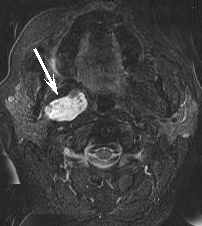

CT SCAN MRI

CT Scan and MR Scan from the same patient on the same day. On the left, metal scatter artifact from metallic fillings in the teeth almost completely obscure a tumor that is easily seen by MRI using metal suppressing techniques on the right.